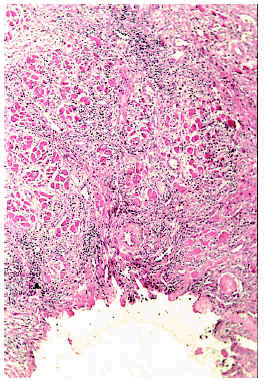

Los hallazgos del examen histológico son muy característicos. Se observa una zona ulcerada de la mucosa cubierta por una capa de exudado fibrinoide con detritus celulares (fig. 11). En la base de la úlcera hay tejido de granulación, con incremento en el número de capilares con células endoteliales prominentes. En los bordes de la úlcera el epitelio aparece hiperplásico. La submucosa está ocupada por un infiltrado difuso compuesto fundamentalmente por eosinófilos y, en cantidad variable, por linfocitos, plasmocitos e histiocitos. El infiltrado con predominio de eosinófilos llega hasta el plano muscular (fig. 12) y las fibras musculares aparecen edematosas y con alteraciones degenerativas127, 131, 134, 138. Hay autores que han descrito la presencia asociada de vasculitis leucocitoclástica138.

Fig. 11.--Úlcera eosinofílica: aspecto histológico. Cortesía de la doctora Emilia Fernández (Salamanca).

Fig. 12.--Úlcera eosinofílica: aspecto histológico. Cortesía de la doctora Emilia Fernández (Salamanca).